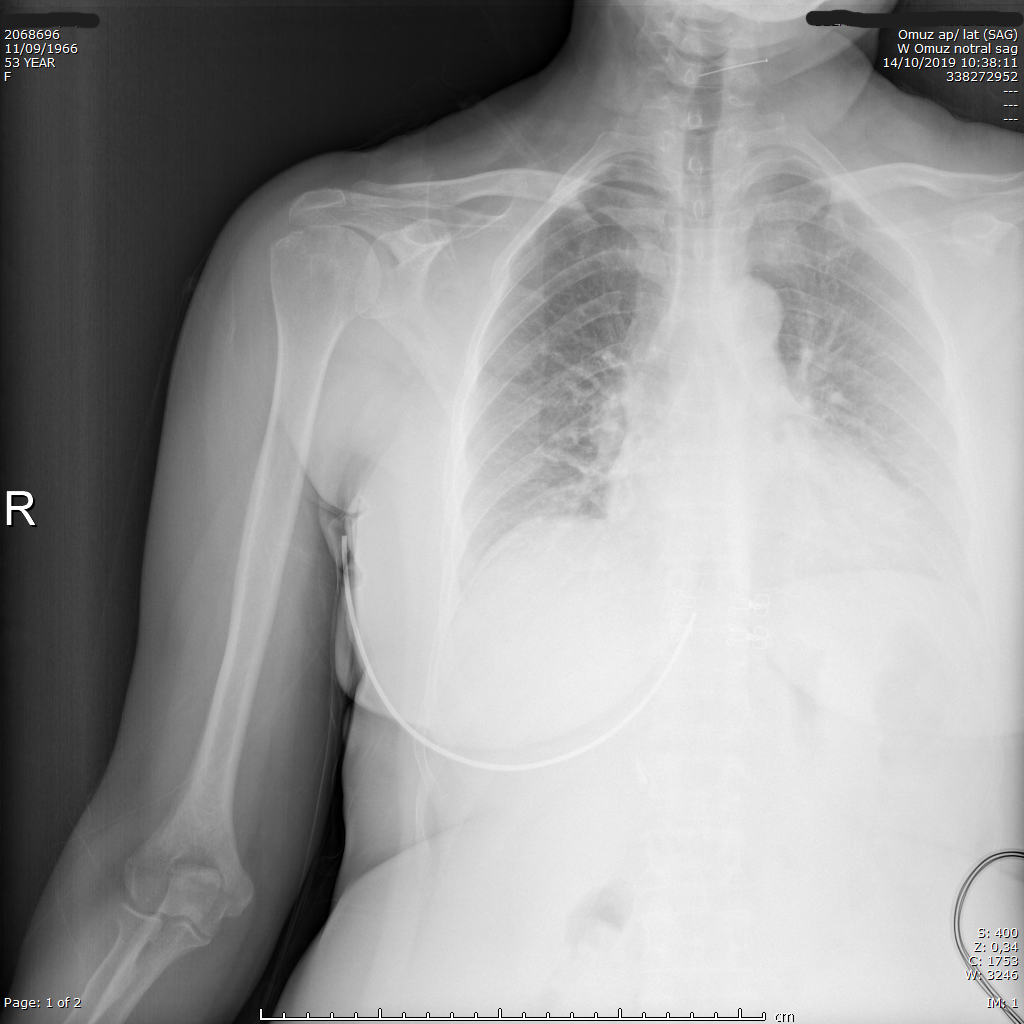

Preoperatif omuz röntgeni — daralmış AHD